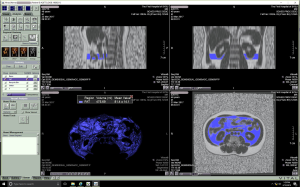

Measurement of VAT volume

Each participant’s fat fraction maps were imported into the processing workstation (Vitrea fX VES, Vital, Minnetonka, MN, USA). The workstation distinguished different tissues according to their signal intensity and automatically selected adipose tissue. After auto-selection, a senior radiologist reviewed and removed the unqualified adipose tissue, such as subcutaneous adipose tissue. Adipose tissue was measured 3 times, and the mean value was identified as the final data. The VAT volume corresponding to the 2nd and 3rd lumbar vertebral levels (VATV L2 and VATV L3) were extracted, respectively, and the sum of VATV L2 and VATV L3 was then computed and considered the total VATV (Figure 1).